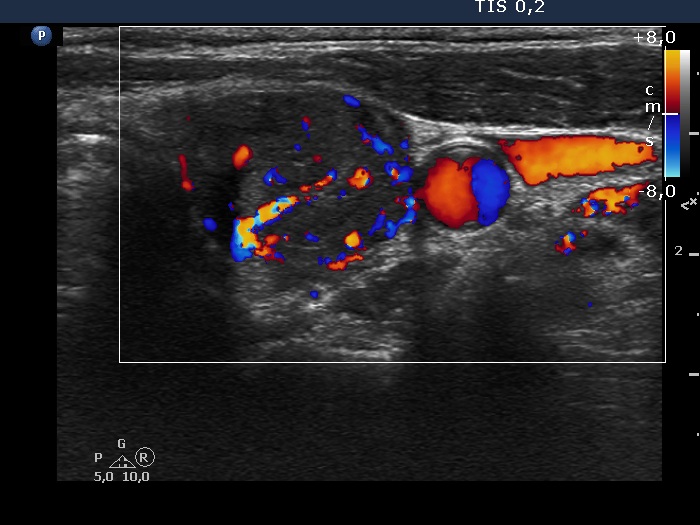

Left lobe, transverse scan, color Doppler mode. The vascularization is increased.